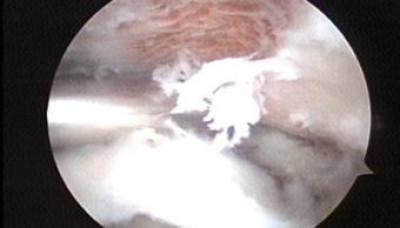

Foto 1 y 2, se observa durante la artroscopía el fresado del acromión